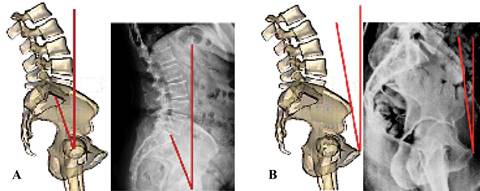

Inclinación pélvica (pelvis tilt). La definición de «pelvis tilt» está sujeta a una seria controversia. Los cirujanos de columna definen al «pelvis tilt» como el ángulo que forman el plano coronal y una línea dibujada desde el centro de las cabezas femorales (eje bicoxofemoral) al punto medio de la plataforma sacra (Figura 14A). Esta definición es útil en cirugía de columna, ya que se emplea para estudiar el balance sagital global atendiendo principalmente los centros de gravedad, tanto en columnas normales como patológicas. Lo anterior es de escasa utilidad en cirugía artroplástica de cadera cuando se estudia la posibilidad de luxación.

En cirugía de cadera se prefiere definir a la inclinación pélvica (pelvis tilt) tomando en cuenta la positividad o negatividad del ángulo formado entre plano anterior de la pelvis y la línea del plano coronal (Figura 14B). La razón de utilizar esta última definición es porque el interés de un cirujano artroplástico de cadera es la correcta colocación del componente protésico acetabular. Es importante considerarla ya que sabemos que la rotación pélvica modifica la anteversión acetabular.